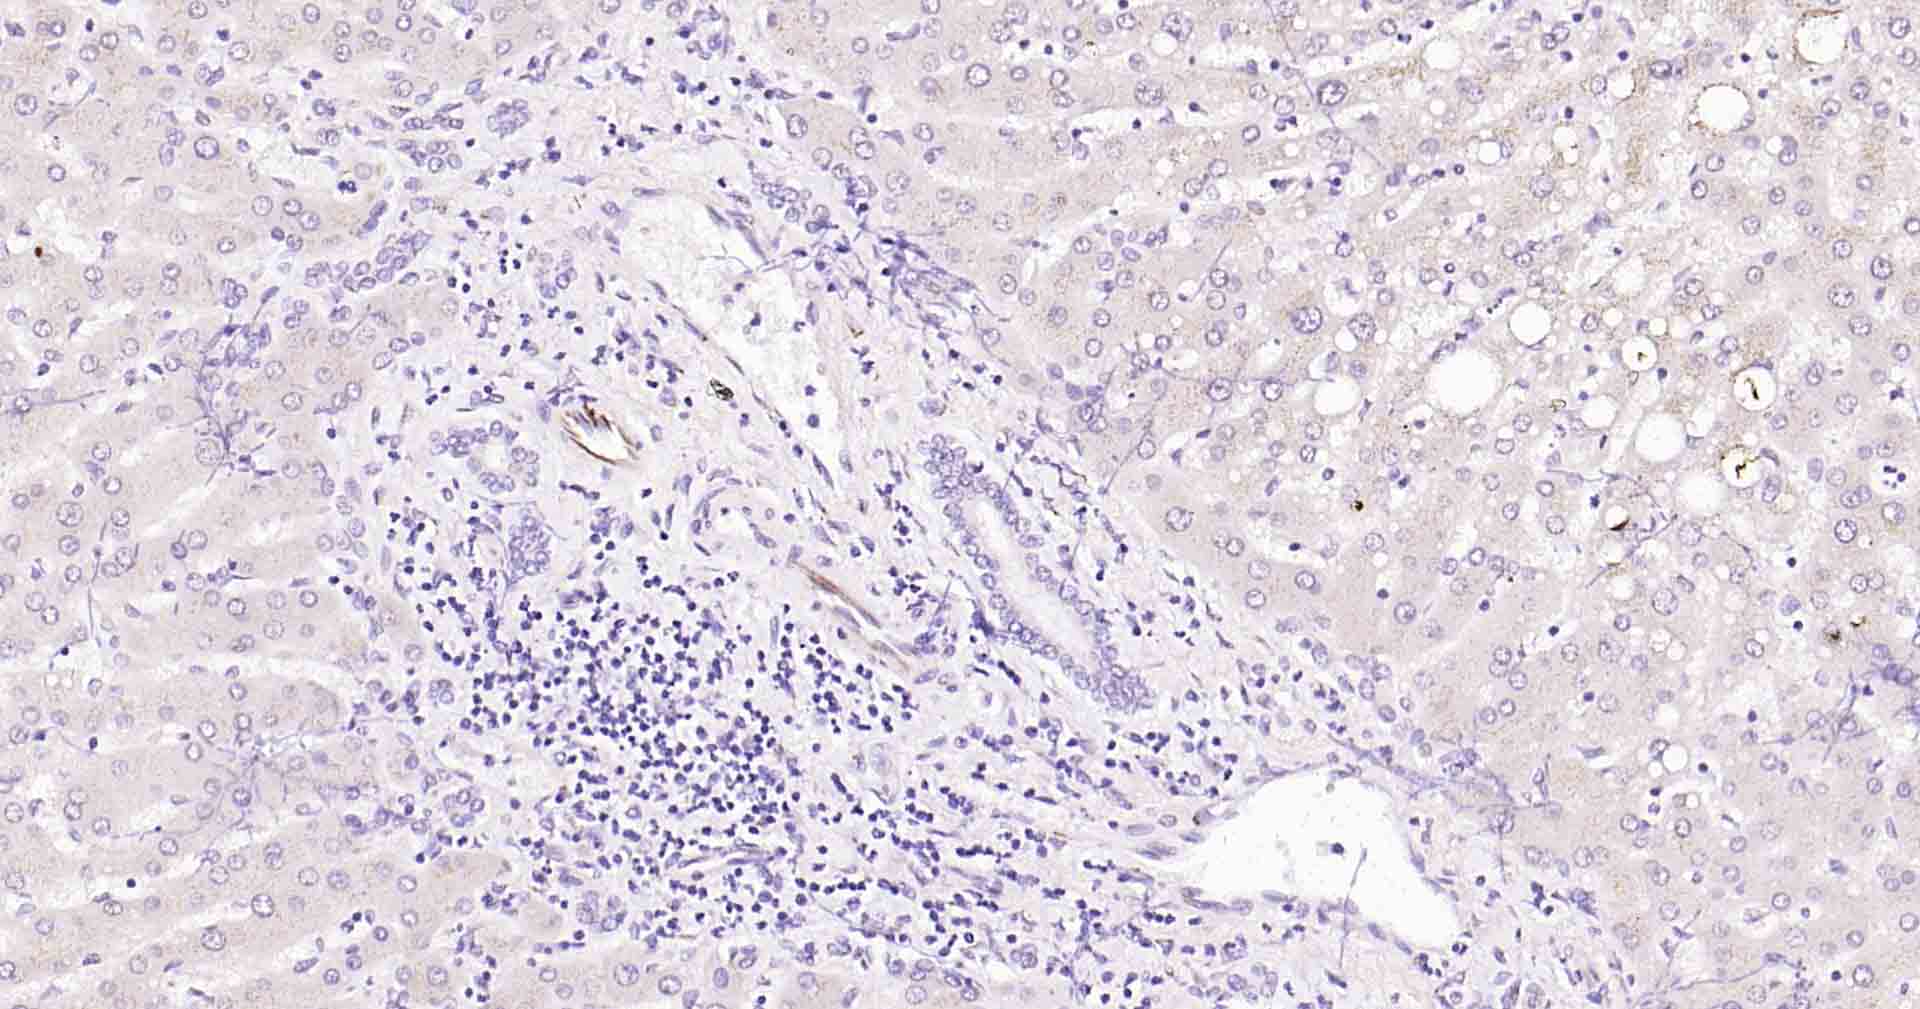

| IHC-P | Human, Mouse, Rat | 1:100-200 | |